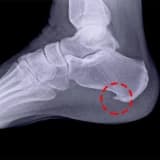

- Sümük Kəsimi: İlk mərhələdə müvafiq sümük cərrahi yolla kəsilir.

- Fiksatorun Yerləşdirilməsi: Açılan sümüklərin ətrafına xarici fiksator aparatı bağlanır.

- Tədrici Uzatma: Aparatın köməyi ilə hər gün sümük tədricən açılır və arada boşluq yaradılır.

- Sümük Toxumasının Formalaşması: Yaranan boşluq zamanla yeni sümük toxuması ilə dolur.

- Sərtləşmə və Aparatın Çıxarılması: Optimal uzunluğa çatdıqda proses dayandırılır; sümük tam sərtləşdikdən sonra aparat kiçik bir əməliyyatla çıxarılır.